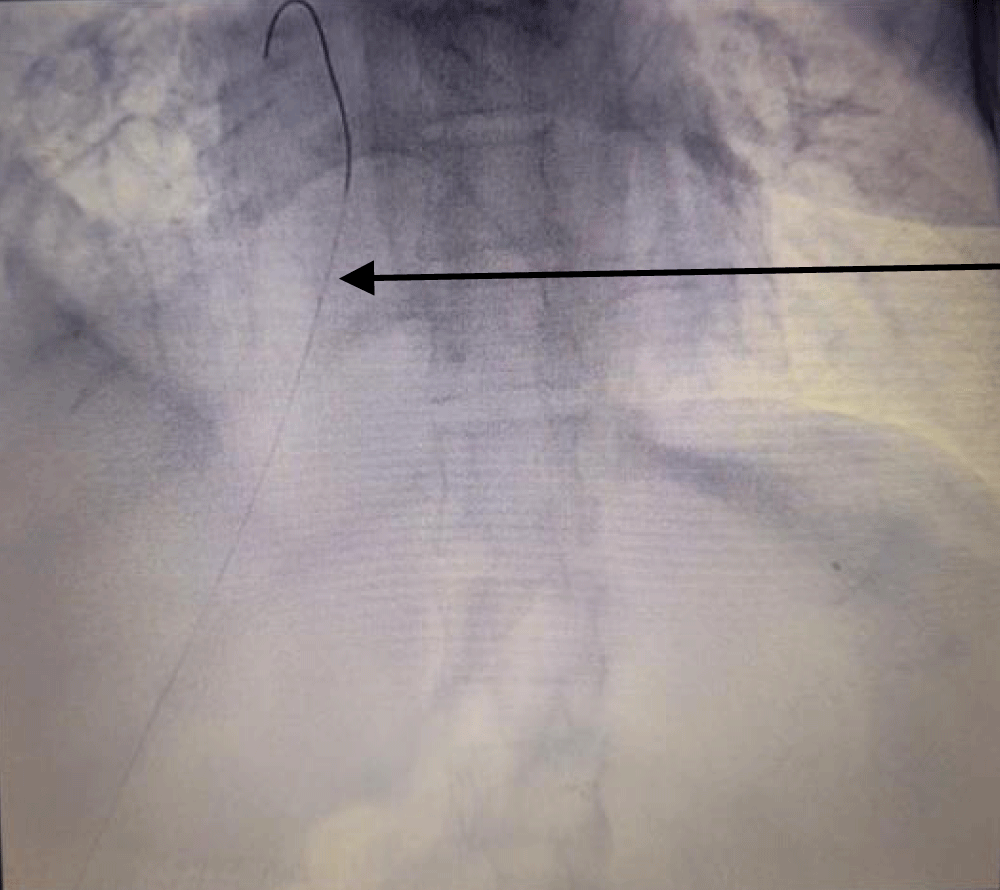

The patient was taken to the cath lab where the procedure was done under ultrasound and fluoroscopy guidance. The procedure was done with a sterile technique and using anti-septic measures; in the cath lab. After cleaning and draping the abdomen, first the right hepatic vein was visualized via ultrasound, and it was punctured by a Chiba needle via the percutaneous route. A guide wire was passed and its position was traced by ultrasound (Figure 1) and fluoroscopy (Figure 2). Radial artery sheath and Kumpe catheter were used as needed to negotiate guide wire in the inferior vena cava and right atrium. A subcutaneous tunnel of 5 cm was created and a tunnelled dialysis catheter was pulled through it (Figure 3). Contrast was injected into the sheath to visualize its flow. The contrast was seen flowing in the right atrium confirming the correct position of the sheath and the kumpe wire (Figure 4). The guide wire was then reinserted into the sheath. As the guide wire reached the inferior vena cava, it was negotiated to the right atrium. This was followed by the removal of the sheath and kumpe wire. After confirming the position of the guide wire in the right atrium (Figure 2), sequential dialation of the tract was done by dilators 6 fr, 8 fr, 10 fr, 12 fr, 14 fr, and finally 14.5 Fr x 19 cm trans-hepatic tunneled dialysis catheter was secured along with subcutaneous tunnel (Figures 5,6). The catheter tip was kept at the junction of the right atria – inferior vena cava (Figure 5). Ultrasound of the liver was done to rule out haemorrhage. There was slight post-operative pain post catheter insertion which subsided after a while. She was kept in the intensive care unit for a day for monitoring of vitals and was moved to the ward the next day. The procedure was uneventful. After being discharged, the patient underwent multiple sessions of hemodialysis with this access. She was told to take proper hygiene care of the area where the catheter was inserted to prevent catheter-related bloodstream infections. She once had an upper respiratory tract infection following which she had poor flow from the tunneled trans-hepatic dialysis catheter. She underwent repositioning of the catheter in the cath lab following which good flow was achieved. She was explained to avoid forceful coughing which can displace the catheter from its position; hampering the flow.

Figure 1: Guide wire (arrow pointing at it) traced via ultrasound in the inferior vena– cava after puncturing the right hepatic vein by Chiba needle and inserting the guide wire.